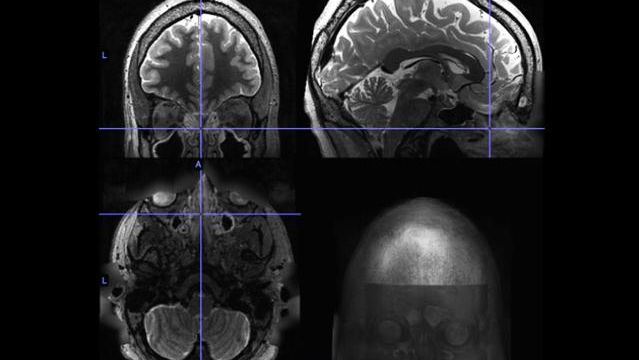

The researchers identified a study cohort from the Human Connectome Project, an open-access, brain-focused dataset of 1,206 healthy adults ages 22-35. Data included radiology image scans and cognitive/behavioral measurements. The scans enabled them to identify 22 people with moderate or severe sinus inflammation as well as an age- and gender-matched control group of 22 with no sinus inflammation. Functional MRI (fMRI) scans, which detect cerebral blood flow and neuronal activity, showed these distinguishing features in the study subjects: